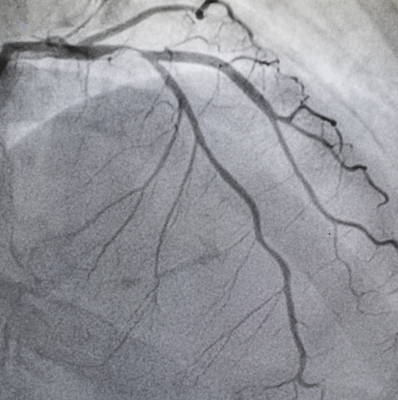

Stent işlemi koroner damarın içine ilerletilen saç teli inceliğinde bir telin üzerinden özel bir ilerletici sistem ile gerçekleştirilir. Bir balon üzerine sıkıştırılarak yerleştirilmiş stent darlığın olduğu koroner damara ilerletilir ve tam darlığın olduğu noktaya, monitörlerde milimetrik olarak tespit edilerek implante edilir. Günümüzde stent işlemi genellikle anjiyo ile birlikte aynı seansta yapılabilmektedir. Doktorunuz sizi bilgilendirip devam etmenin uygun olduğunu söyleyebilir.

Farklı açılardan kontroller yapılarak sorunlu damarın açıldığı teyid edilir. İçerideki tüm teller ve katederler dışarı çıkarılır. El bileğindeki veya kasıktaki kılıf çekilir ve bandaj yapılır. Hasta odasına alınır. EKG, tansiyon ve nabız kontrolleri yapılır. Özel bir durum yoksa hemen yemek yiyebilir ve su içebilir. El bileğinden yapıldıysa hemen ayağa kalkabilir. Kasıktan yapıldıysa 6-12 saat yatması gerekebilir. Ertesi günün sabahından kontroller yapıldıktan sonra ilaçlar ve sağlıklı yaşam hakkında öneriler yapılarak taburcu edilir. Bir ay sonrası için kardiyoloji randevu ayarlanır.